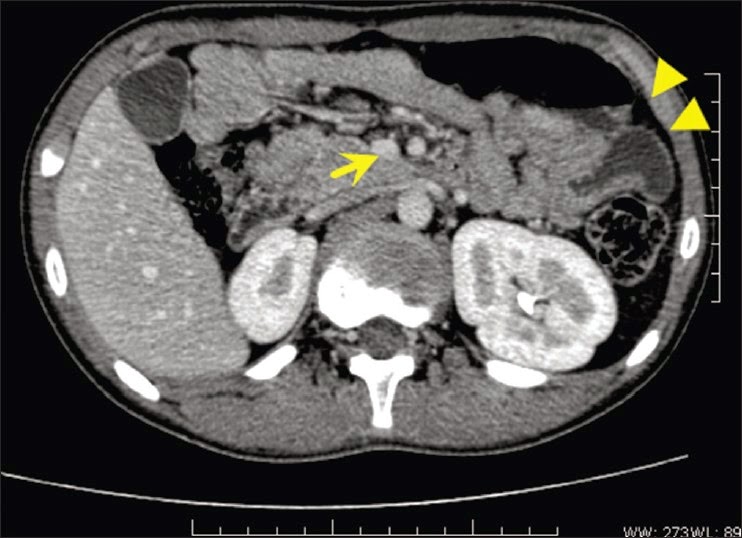

Мезентеріальний тромбозНе менш складною в таких ситуаціях є діагностика гострої мезентеріальної непрохідності особливо в тих випадках, коли ембол або тромб фіксується в так званому третьому сегменті верхньої брижової артерії, тобто в ділянці артерії, що кровопостачає термінальну частину здухвинної кишки. При цьому вся клінічна картина розпочинається з поступово наростаючих болів у правій здухвинній ділянці на фоні високого лейкоцитозу. Це і є основною причиною розкриття черевної порожнини доступом Дьяконова-Волковича, коли через ще не розкриту очеревину просвічує темного кольору кров'яниста рідина, що по розкритті очеревини вільно витікає в рану і має іхорозний запах. В таких випадках хірург може подумати, перш за все, про панкреонекроз. У зв'язку з цим він виконує ревізію термінального відділу здухвинної кишки, яка має темно-коричневий колір, потовщена, щільна і не перистальтує. Це достовірний доказ гострої мезентеріальної непрохідності, що диктує подальший хід операції з ревізією всього кишківника і верхньої брижової артерії через серединну лапаротомію.